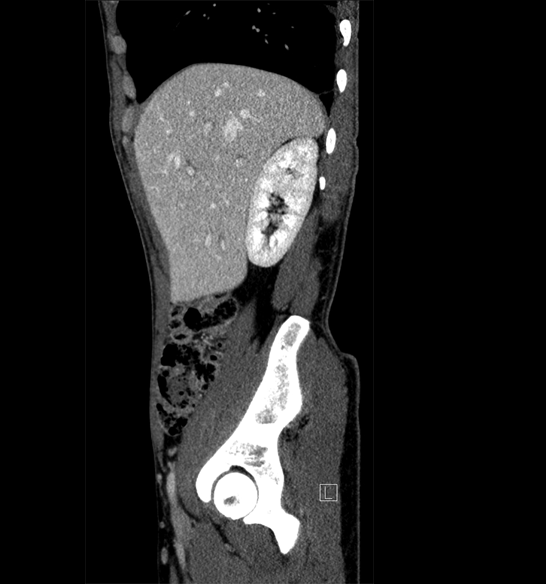

Body

Covers abdominal CT anatomy.